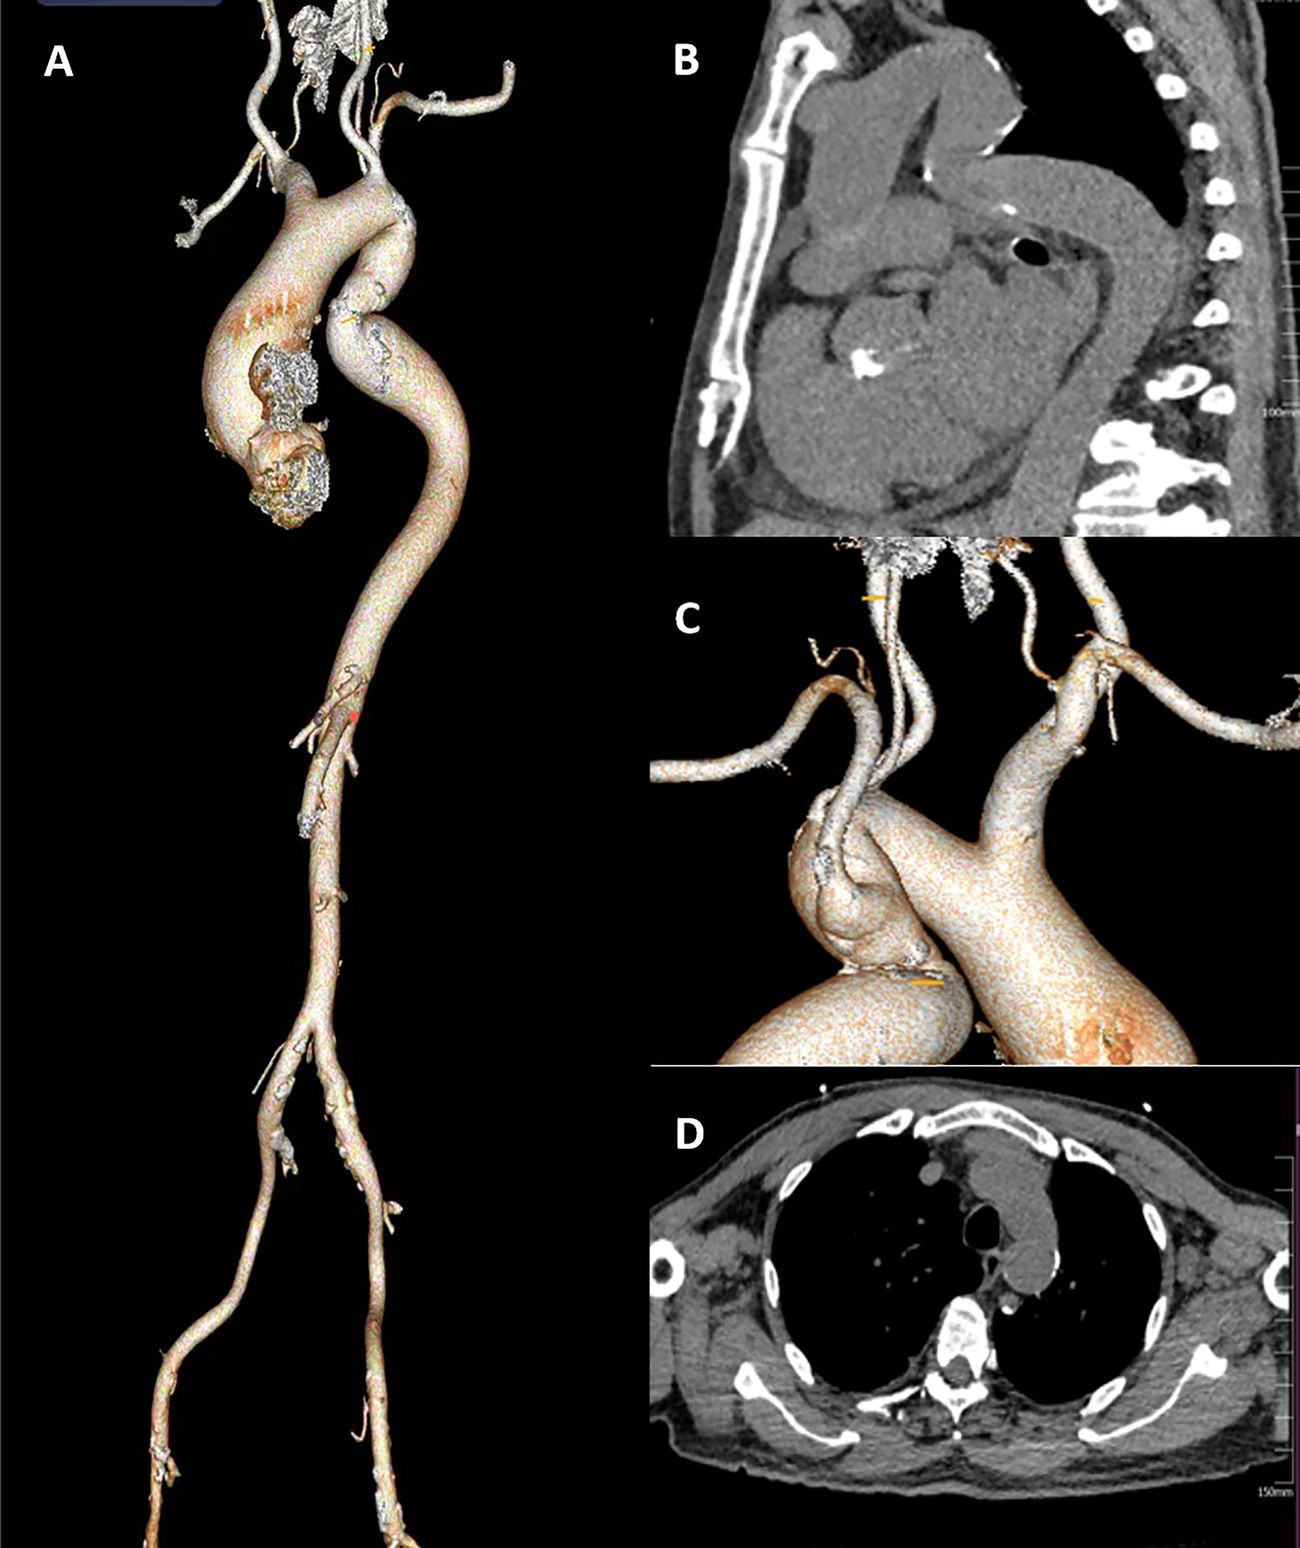

This patient had severe AS combined with CAD. His descending aortic arch has a localized tortuosity (Figures 1A,B), while the left common carotid artery is free from stenosis or calcification, and the Willis circle is complete. The right vertebral artery is dominant, and the pathway from the left common carotid artery to the annulus is feasible, the left subclavian artery was relatively small in diameter, and the right subclavian artery showed marked angulation (Figure 1C). Chest CT demonstrated a minimal descending aortic diameter of 21 mm at the narrowest segment, with no significant caliber change compared to adjacent normal segments and no evidence of collateral vessel formation (Figure 1D). Following Multi-Disciplinary Team (MDT) discussion and with the consent of the family, a transcarotid, one-stage TAVR procedure combined with PCI was planned.

Figure 1

(A) the full CT of the aorta. (B) a Z-shaped fold tortuosity in the descending aortic arch.(C) the left common carotid artery is free from stenosis or calcification, the Willis circle is complete. The right vertebral artery is dominant. (D) The narrowest segment of the descending aorta).